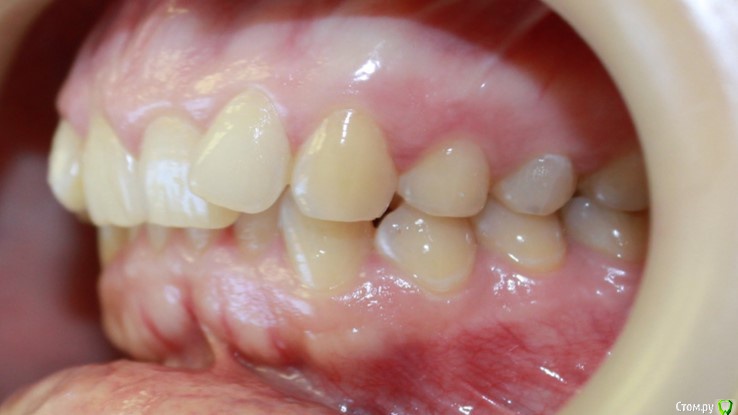

kapyulia Опубликовано 22 декабря, 2017 Поделиться Опубликовано 22 декабря, 2017 Добрый день! Могли бы Вы подсказать есть ли необходимость в удалении зубов (пятерки) с верхней челюсти? Спасибо за помощь. Ссылка на комментарий

Brigita Опубликовано 24 декабря, 2017 Поделиться Опубликовано 24 декабря, 2017 Сложно сказать без очного осмотра, по фото показаний нет. Ссылка на комментарий